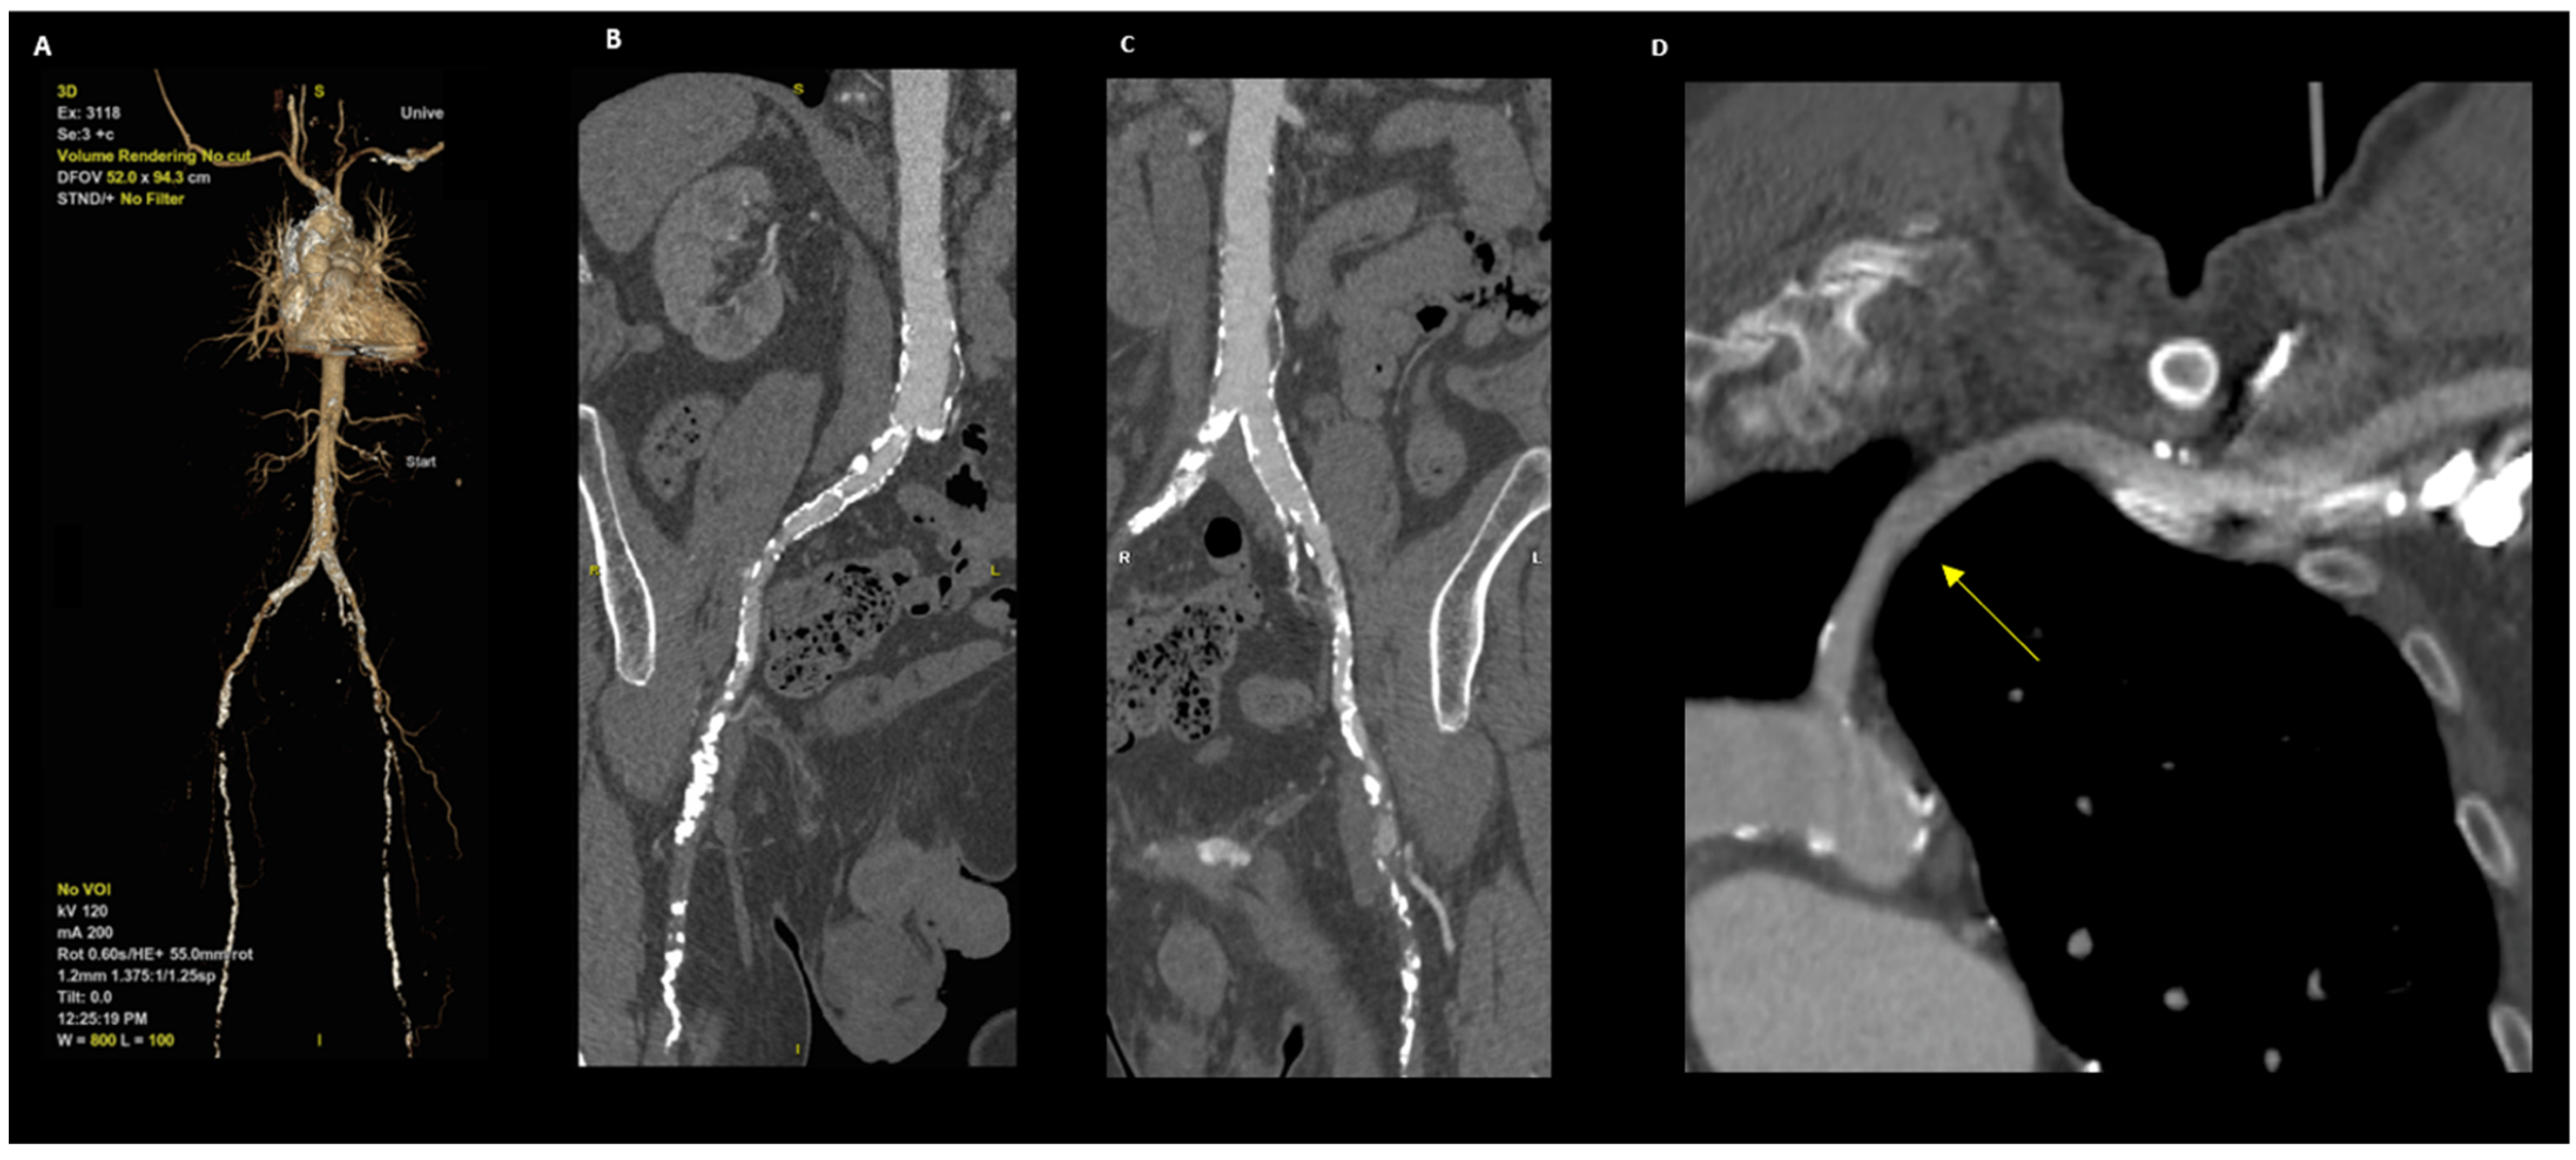

2.2. Transaxillary Technique